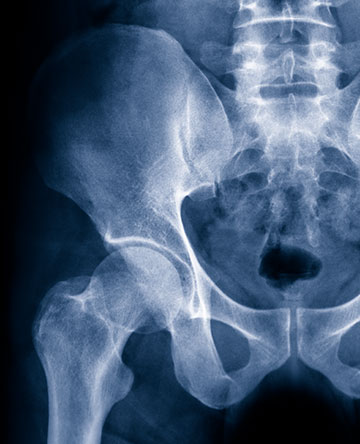

The diagnosis and treatment of disorders of the hip has advanced significantly over the last decade. Most problems can be treated with non surgical methods such as Physical therapy, medications and selective injections.

Arthroscopic procedures can be used to treat conditions such as labral tears, femoral acetabular impingement, loose body removal, chodroplasty. When hip preservation is not possible, joint replacement procedures can restore function and relieve pain. For the right patients, Hip Resurfacing can, effectively treat arthritis and improve quality of life. Even traditional hip replacement has seen significant improvement with better implants, minimally invasive approaches, and multi-modal pain control techniques. These combine to make surgery and rapid recovery much easier.